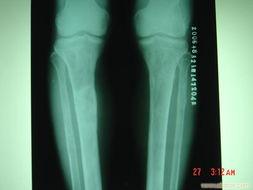

这张骨坏死照片,让我第一次直观地感受到了这个疾病的严重性。照片中,一个患者的关节部位出现了明显的磨损和变形。你可以看到,原本光滑的关节表面变得粗糙,甚至出现了凹凸不平的痕迹。这就是骨坏死,一个无声无息地侵蚀你健康的“隐形杀手”。

这张骨坏死照片,让我深刻地认识到了这个疾病的严重性。它提醒我们,要关注自己的身体健康,及时发现并治疗疾病。同时,也要关爱身边的人,帮助他们战胜病痛,重拾健康的生活。